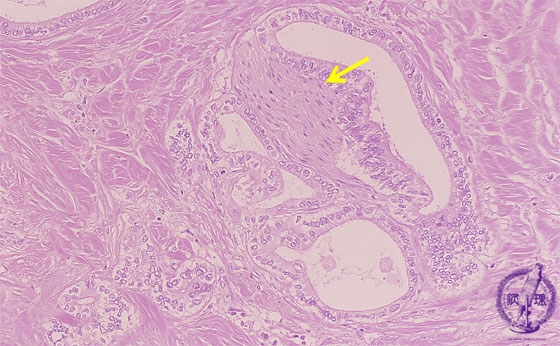

- ★(13)Intrahepatic bile duct cancer (adenocarcinoma)

Microscopic image (HE stain, intermediate power): Neuronal invasion (yellow arrow) by tubular adenocarcinoma is seen.